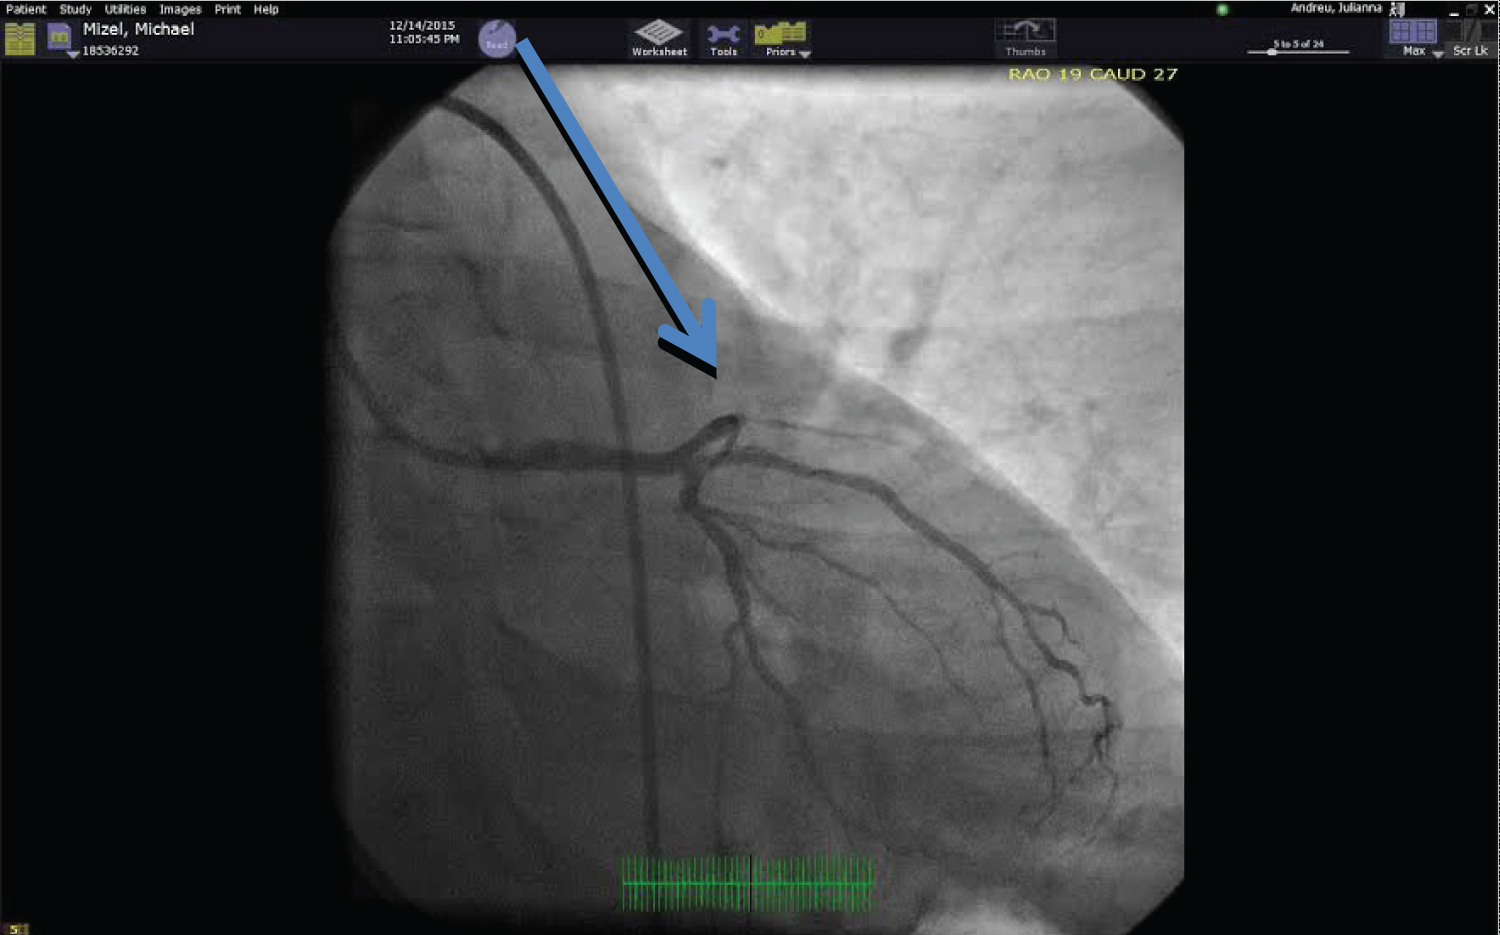

The ECG post-delivery revealed loss of R waves across the precordium (Figure 1). This retrospectively raised a strong suspicion that the initial insult was an unrecognized coronary artery dissection versus a paradoxical embolism across the ASD to the coronary circulation. The interventional team felt the angiogram was supportive of a dissection. This infarct was supported on MRI and TEE imaging. Surgery was consulted for evaluation of the sinus venous ASD in the setting of enlarged right heart chambers by echocardiography and MRI. The review of the MRI revealed normal venous connections. Because of the apical infarct, surgery requested a cardiac catheterization. The catheterization revealed an occluded left anterior descending coronary artery (Figure 4). This occluded vessel retrospectively identified the etiology of the post-delivery hemodynamic instability. The patient was feeling well and elected not to pursue surgery for the ASD or coronary disease.

Figure 4: Coronary angiography reveals an occluded LAD (Blue arrow). View Figure 4